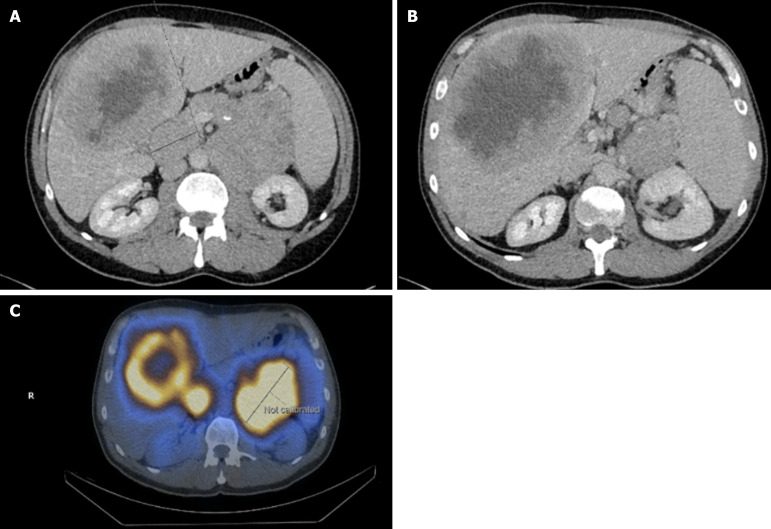

胰腺神经内分泌肿瘤(pNETs)是罕见的,在及时诊断和后续治疗方面提出了重大挑战。这些肿瘤的临床和病理生物学行为差异很大,使得临床医生的随访和治疗方法具有挑战性。虽然这些肿瘤大多数是激素不活跃的,但有些可能与内分泌功能障碍有关。非常罕见的是,非功能性肿瘤后来会变得激素活跃,进一步使预后和治疗复杂化。根据疾病的特点、临床表现和预后,制定了不同的治疗方式,效果也各不相同。我们最近遇到了一个独特的晚期无功能恶性pNET病例,诊断为转移性疾病,医学上使用生长抑素类似物治疗(奥曲肽)和靶向治疗(依维莫司),病情稳定40个月,随后变成功能性(胰岛素瘤)。在这一独特病例的帮助下,我们在这篇基于证据的综述中更新了目前pNETs的临床、诊断和治疗方法。

Pancreatic neuroendocrine tumors (pNETs) are rare, presenting significant challenges in timely diagnosis and subsequent treatment. The clinical and pathobiological behavior of these tumors varies significantly, making follow-up and therapeutic approaches challenging for clinicians. Although the majority of these neoplasms are hormonally inactive, some can be associated with endocrine dysfunction. Very rarely, a nonfunctional tumor can later become hormonally active, further complicating prognostication and management. Depending on the character of the disease, clinical picture and prognosis, different treatment modalities are instituted with varying effectivities. We recently came across a unique case of nonfunctioning malignant pNET at an advanced stage, metastatic disease upon diagnosis, managed medically with somatostatin analog therapy (Octreotide) and targeted therapy (Everolimus) with stable disease for 40 months that subsequently turned out to become functional (insulinoma). With the aid of this unique case, we update the current clinical, diagnostic and therapeutic approach to pNETs in this evidence-based review.